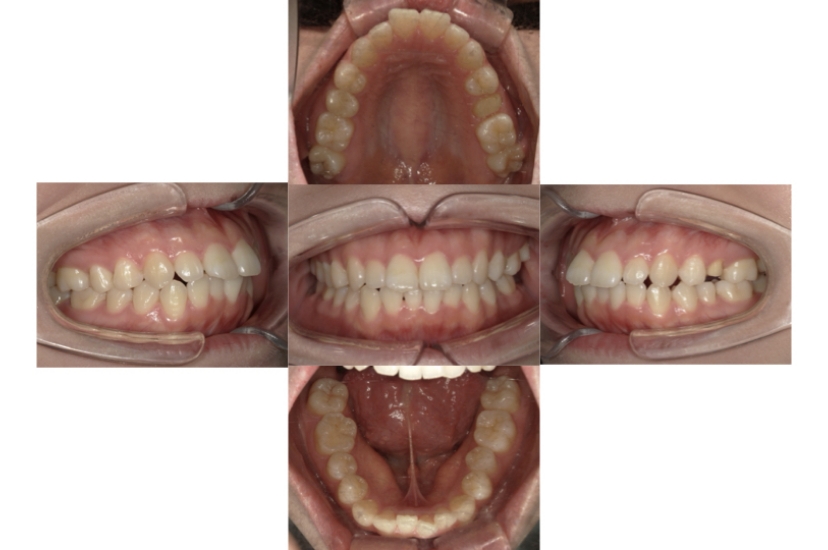

BEFORE

AFTER

症例1

上顎前突、叢生

抜歯

ブラケット矯正

上下顎叢生、上顎前突(出っ歯、上下の前歯のガタガタ)のケースです。

装置はラビアル(上下表側)で、上顎の小臼歯を2本抜歯を行っています。抜歯したスペースを使って、上の前歯の後方移動と叢生(ガタガタ)と出っ歯の改善を行っています。下は歯と歯の間にIPR(隣接面削合)を行い、スペースを確保し、叢生の改善を行っています。

主訴 前歯のガタガタと出っ歯が気になる。

年齢・性別 47歳 女性

お住まいの地域 神奈川県川崎市

治療方針 抜歯スペースおよびIPRを利用して上前歯の叢生(ガタガタ)の改善

抜歯部位 上顎左右第一小臼歯

使用装置 ラビアル(上下表側)、顎間ゴム

治療期間 2年0か月

治療回数 15回

リテーナー クリアリテーナー